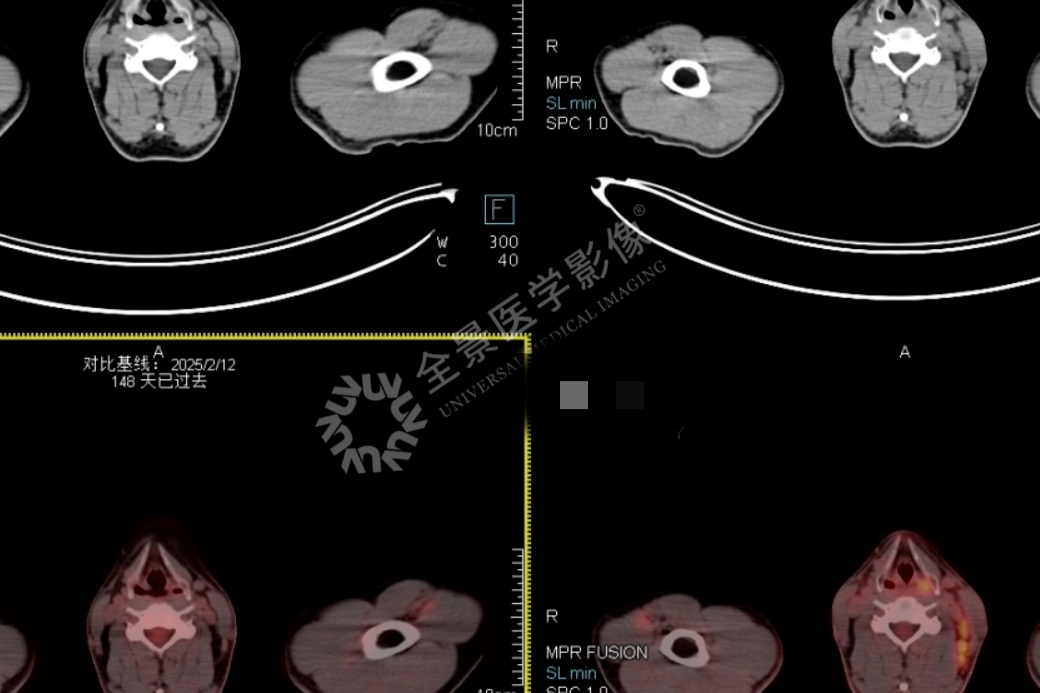

淋巴瘤治疗显成效!PET/CT 见证病灶「大撤退」

淋巴瘤治疗显成效!PET/CT 见证病灶 「大撤退」